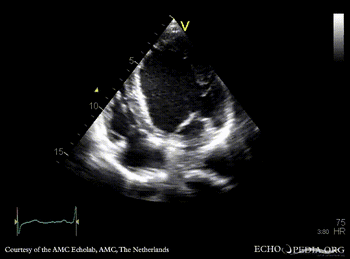

PLAX: Color Doppler, severe aortic regurgitation A4CH: dilated left ventricle